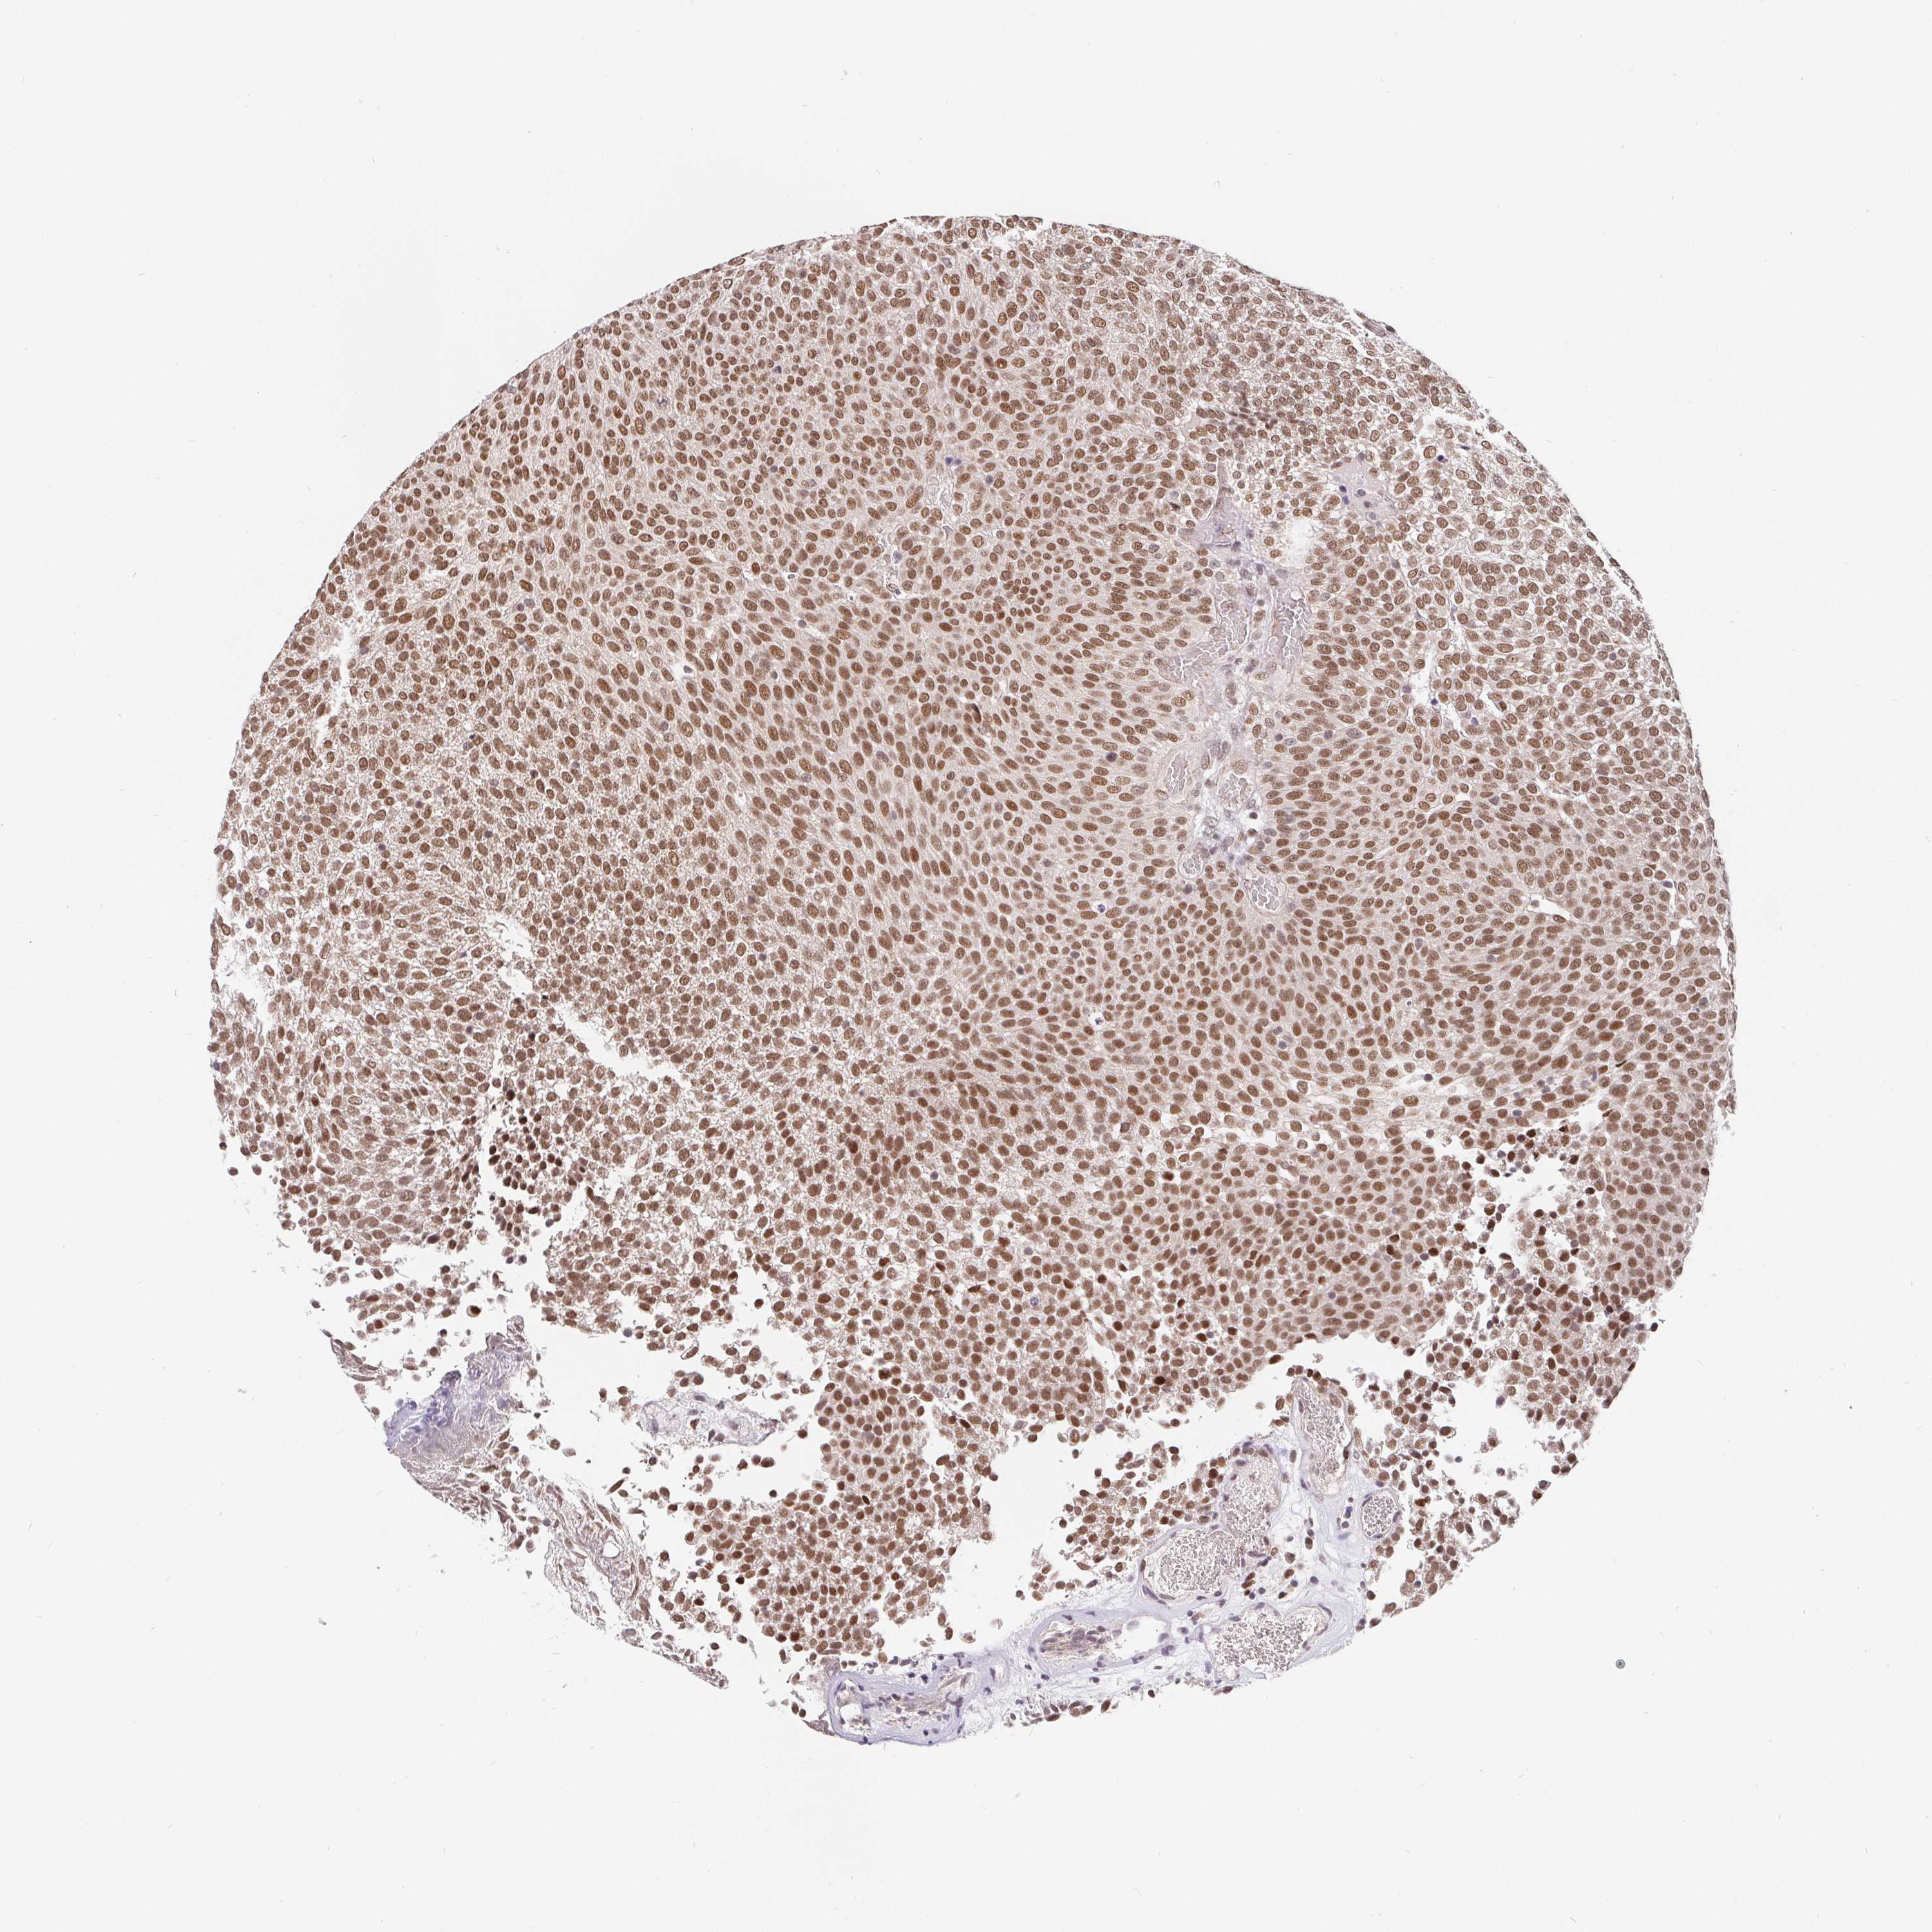

UROTHELIAL CANCER - Protein expressioni

A mouse-over function shows sample information and annotation data. Click on an image to view it in a full screen mode. Samples can be filtered based on level of antibody staining by selecting one or several of the following categories: high, medium, low and not detected. The assay and annotation is described here.

Antibody stainingi

Antibody staining in the annotated cell types in the current human tissue is reported as not detected, low, medium, or high, based on conventional immunohistochemistry profiling in selected tissues. This score is based on the combination of the staining intensity and fraction of stained cells.

Each image is clickable and will lead to virtual microscopy that enables deeper exploration of all samples and also displays staining intensity scores, fraction scores and subcellular localization as well as patient and tissue information for each sample.

Antibody HPA064323

Antibody CAB002608

Staining

High

Medium

Low

Not detected

Intensity

Strong

Moderate

Weak

Negative

Quantity

>75%

75%-25%

<25%

None

Location

Nuclear

Cytoplasmic/membranous

Cytoplasmic/membranous,nuclear

Urothelial carcinoma, High grade

Urothelial carcinoma, NOS

Urothelial carcinoma, Low grade

Adenocarcinoma, NOS